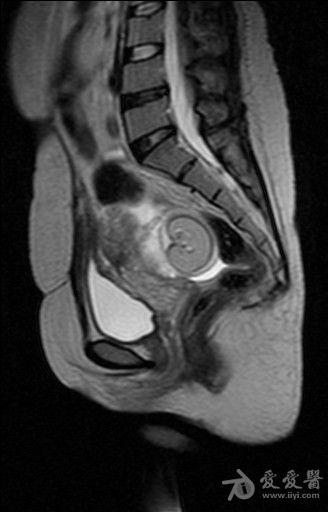

体检发现盆腔包块入院检查(较典型病例MRI平扫加增强)。

病史如题。图像如下。 T2

含有脂质信号,边缘清楚,考虑畸胎瘤